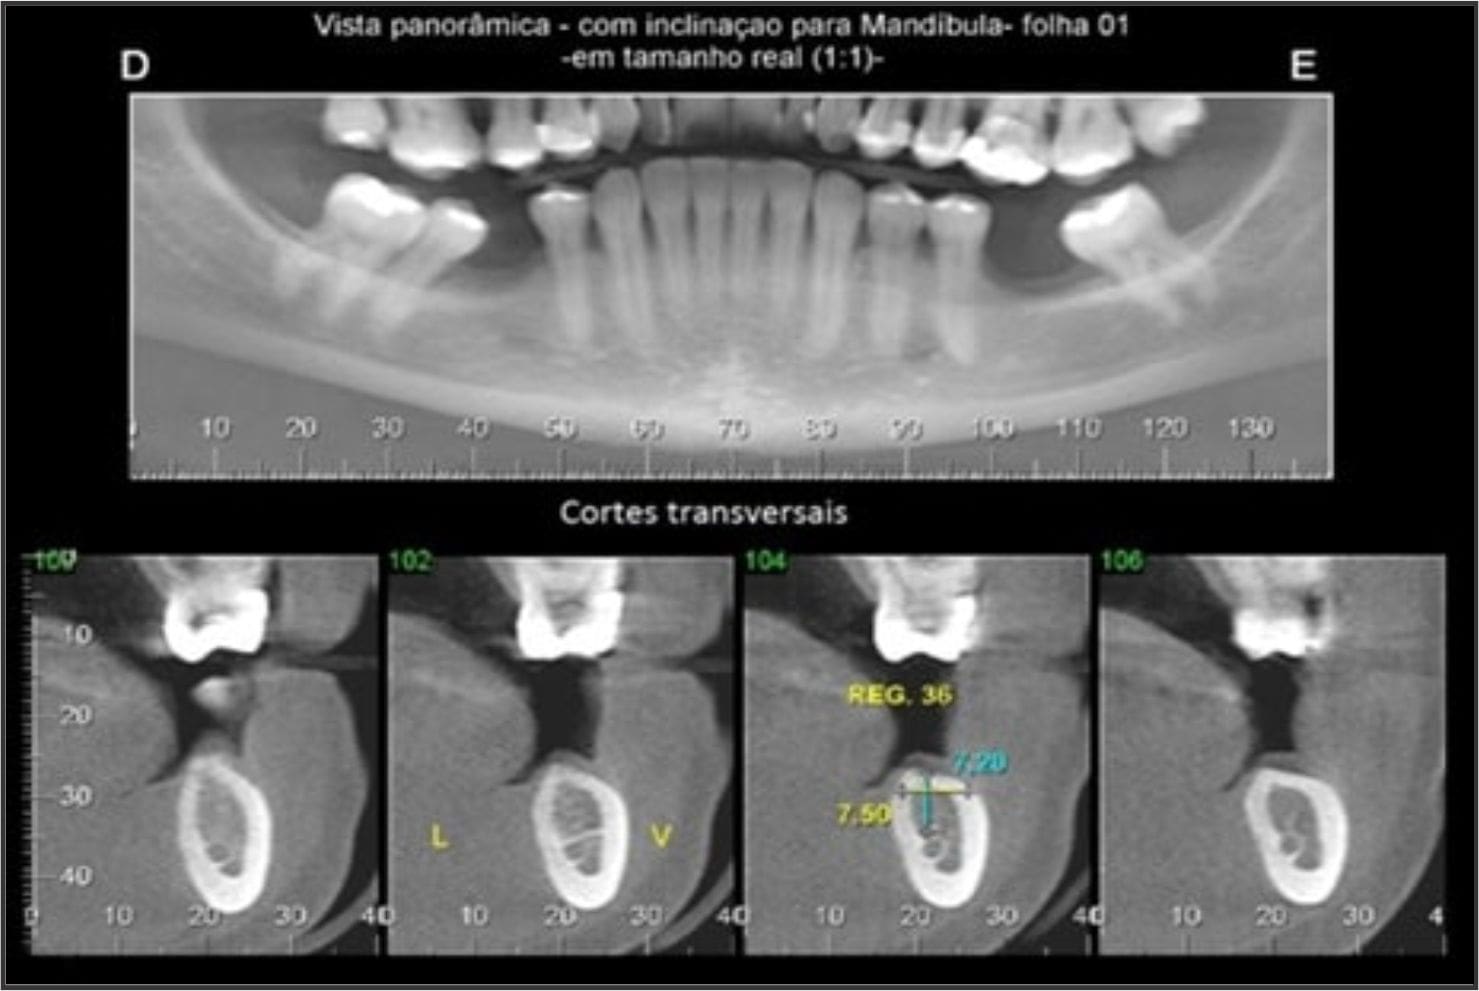

RADIOGRAFIAS DIGITAIS

Radiografia Panorâmica

Radiografia de ATM